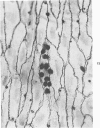

In rats with diet-induced hypercholesterolemia, two concomitant changes began to occur within 1 week and persisted for 1 year: an increase in total plasma cholesterol and an increase in the number of mononuclear cells adhering to the aortic intima (up to values 50 times normal). Adherent cells were approximately 90% monocytes and approximately 10% lymphocytes. Adhesion was focal, with some preference for ostia of aortic branches; it was followed by migration into the subendothelial space. The subendothelial monocytes/macrophages progressively became foam cells, thus giving rise to microscopic "fatty streaks." Ultimately, typical atherosclerotic plaques were formed. Four possible mechanisms of increased cell adhesion are suggested. Endothelial changes were mild; myelin figures arising from the endothelial surface were seen by electron microscopy. Endothelial denudation was never observed, neither in light-microscopic preparations stained with AgNO3 nor by ultrastructure. Platelet participation was minimal. It is concluded that in this model atherosclerotic plaques are initiated by mononuclear cell adhesion and emigration; endothelial denudation is not a necessary step in their pathogenesis.